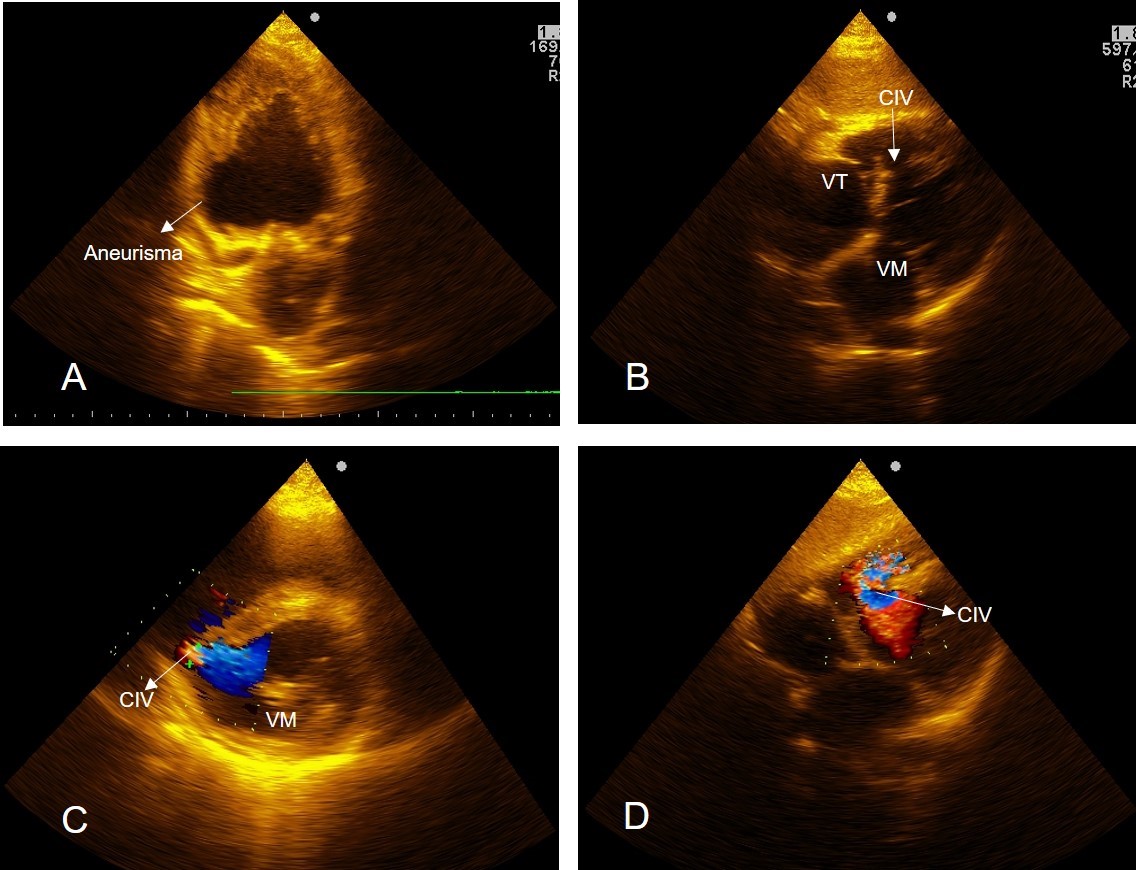

La ruptura del septum interventricular post infarto del miocardio es una complicación mecánica poco frecuente, pero de muy alta mortalidad. Se presentan dos casos que estuvieron hospitalizados en una Unidad de Cuidados Coronarios de un Hospital General, a los cuales se les realizó ecocardiograma transtorácico y se corroboró, en ambos, la existencia de ruptura del septum interventricular inferior como complicación de infarto del miocardio de cara inferior, uno de ellos con extensión al ventrículo derecho. Posteriormente se analizan varios aspectos comunes y no comunes entre los dos casos presentados, que pudieran explicar la diferente evolución que tuvieron estos pacientes.